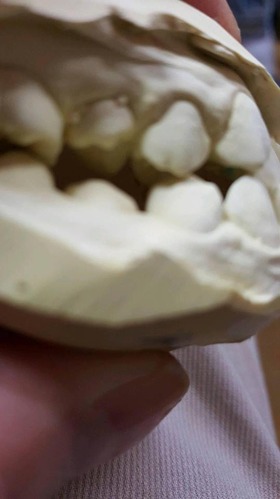

1、先ず一番目は、10才、右の前歯が反対咬合と言って上の歯と下の歯が逆の位置にあり、他の部分があまり咬合していない10才の子供の例でした。噛むと痛みが突然出てしばらく続いていたという症例。

診断を咬合性(歯と歯の噛みあわせ)の急性歯髄炎(神経の炎症)と判断したが、では治療はどうすればいいのかという相談。

レントゲンと話の内容から、食いしばりや歯ぎしりによるものではなく、単純にぶつかる歯が少ないので、その時に前歯のところで何か硬い物などを噛んだために外傷性の痛みが来たのではないかという判断でした。炎症でもないので、奥歯にマウスピースなどを入れて前歯を当たらなくした後に、症状が緩解したら、反対咬合という上下の前歯の関係を簡単な小矯正で変更した方がいいという診断と治療方針の提案で解決しました。